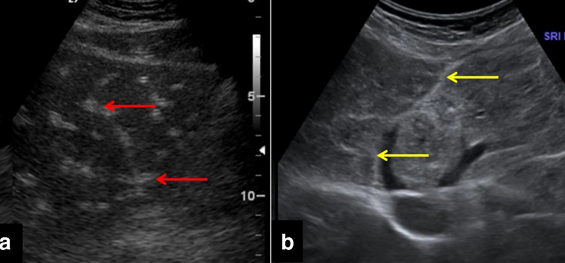

cavernous transformation of PV